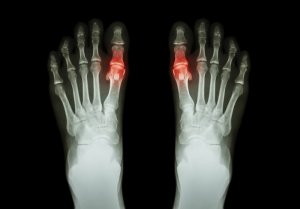

- İlk başlarda, bir ya da birkaç eklem etkilenir. Bu eklemler genellikle, ayak baş parmağı, diz ya da dirseklerdir. Bu ağrılar birkaç gün boyunca görülmeyip ardından yine kendini hissettirmeye başlayabilirler.

- Tipik olarak, etkilenen eklemler sıcak ve kızarık olurlar. Ayrıca genellikle daha hassas ve şişik olurlar.